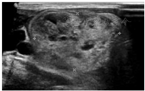

TMNG的甲状腺常比弥漫性甲状腺肿的甲状腺大,通常回声不均匀且合并大小不等及回声不均的结节(图3)。这些结节部分具有功能,部分是无功能的。超声引导下细针穿刺活组织检查(简称活检)一般只考虑穿刺无功能结节,因为甲状腺显像表现为热结节者为肿瘤的概率极低[24]。TAs超声通常表现为实性、等或低回声且边界清楚的结节,结节边缘或结节内、结节周围血供丰富(图4)。